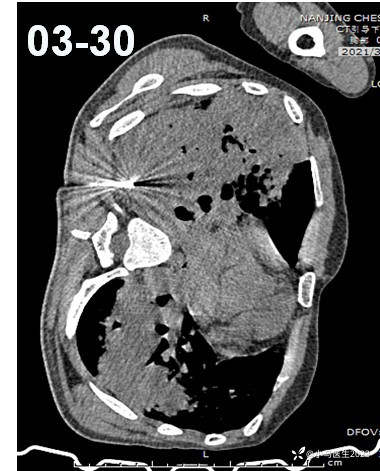

停用激素后病灶增多

骨髓穿刺——排除白血病

经皮肺穿刺

肺实变,肺间质内见大量慢性炎症细胞浸润和微小上皮样肉芽肿形成,特殊染色未见明确病原体,未见嗜酸粒细胞浸润

特殊染色PAS(-),抗酸(-)

结核PCR(-)